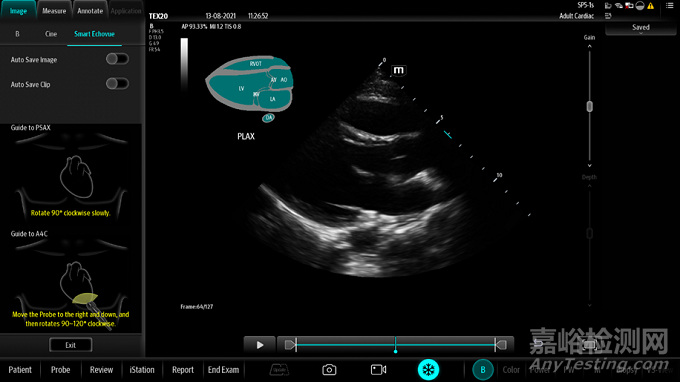

圖4 心臟結構自動識別功能開啟后的操作界面

心臟結構自動識別功能用于臨床超聲診斷檢查。該功能基于美國超聲心動圖學會指南及標準,針對二維超聲心臟圖像使用了深度學習技術進行切面類型識別,即實時判定當前圖像屬于哪個標準切面(例如,心尖四腔、 胸骨旁長軸、胸骨旁短軸、劍下四腔和下腔靜脈), 并進一步識別當前圖像中出現(xiàn)的特征結構,如左室、左房、二尖瓣、三尖瓣等。其中深度學習技術通過對大樣本數(shù)據(jù)的學習獲取圖像特征,一方面進行切面類型分類,一方面進行目標檢測。

操作者按照說明書規(guī)范的操作流程,選擇相控陣探頭及心臟檢查模式,在調整圖像參數(shù)獲取最佳優(yōu)化圖像后,啟動心臟結構自動識別功能。若當前圖像為標準切面,則屏幕上將實時顯示切面類型,并提示圖像上可以辨認的特征結構,該結果僅供醫(yī)生作為參考,醫(yī)生可基于專業(yè)知識進行確認以及修改。